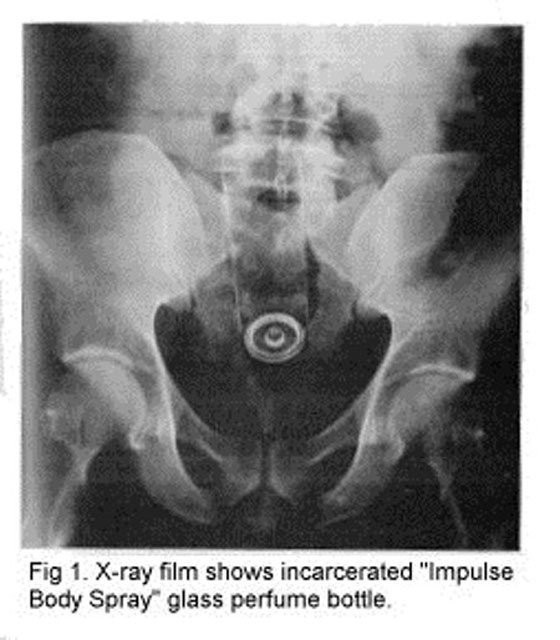

PARFÜM ŞİŞESİ; Anüsünde parfüm şişesinin sıkıştığını söyleyen 39 yaşındaki adam acil servise başvurdu. Daha önce de aynı işlemi yaptığını fakat sorun yaşamadığını söyleyen adam bu sefer sıkışıp kaldığını belirtti.